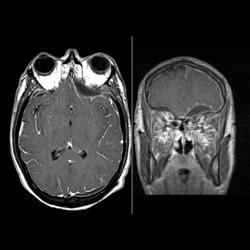

30 yo male presenting with fever and sinusitis initially then depressed level of consciousness. MR and CT